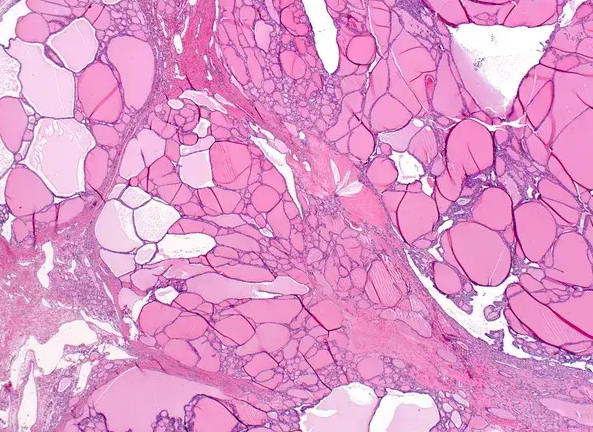

Ιστοπαθολογική εξέταση — Πολυοζώδης βρογχοκήλη (Ευγενική παραχώρηση Dr. V. Penopoulos)